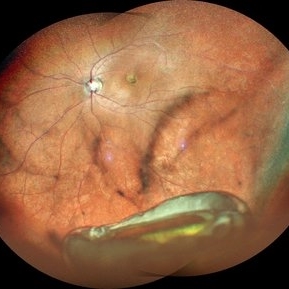

Old Supero-Temporal Branch Retinal Vein Occlusion with Macular Hole Right Eye Fundus

Fundus photograph of a 36-year-old female presented with supero-temporal branch retinal vein occlusion with macular hole in right eye.

Photographer: Dr. Akansha Sharma-Retina Foundation

Condition/keywords: branch retinal vein occlusion (BRVO), macular hole